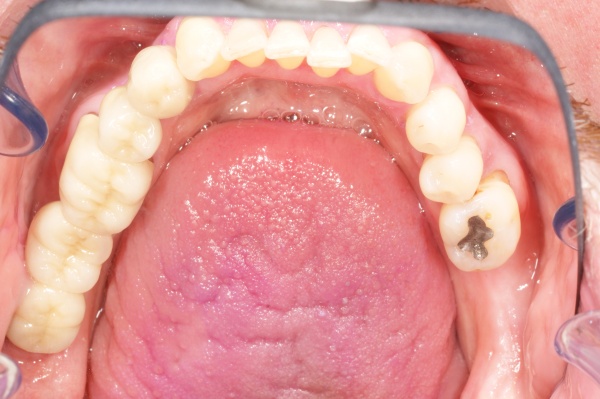

Mit der Transplantation eines freien Schleimhauttransplantats im Januar 2001 konnte die aktive parodontologische Therapie abgeschlossen werden, der Patient wurde zur Unterstützenden Parodontitistherapie in das Recallsystem der FU VIIa aufgenommen. Der Patient stellte sich dabei halbjährlich zur Durchführung von professionellen Zahnreinigungen vor, die durch die bereits beschriebenen Elemente der Erhaltungstherapie ergänzt wurden. Ein wichtiges Element der Erhaltungstherapie ist die regelmäßige parodontale Diagnostik mit der Erstellung eines Parodontalstatus, um gegebenenfalls Rezidive frühzeitig erkennen und behandeln zu können. Im Jahre 2006 kam es an einzelnen Zähnen zu Rezidiven, es konnten Sondiertiefen von bis zu 7mm sondiert werden. Es wurde daher ein Scaling/Rootplaning der rezidivierenden Taschen durchgeführt, an einzelnen Zähnen erfolgten im Jahre 2008 zudem weiterführende parodontalchirurgische Maßnahmen im Sinne von Lappenoperationen (s. Abb. 16). Im Rahmen der unterstützenden Parodontitistherapie erfolgte neben den schon erwähnten halbjährlichen professionellen Zahnreinigungen im November 2012 eine erneute subgingivale Instrumentierung an 21, 24, 28, 41, 46. Die letzte Vorstellung des Patienten erfolgte im April 2015 (s. Abb. 17, 18, 19). Dabei stellte sich die marginale Gingiva entzündungsfrei dar, die approximalen Sondiertiefen betrugen durchschnittlich zwei bis drei Millimeter, geringgradig erhöhte Sondiertiefen verbleiben an 21, 28, 36, 47. Die häusliche Mundhygiene des Patienten stellte sich wie schon über den gesamten Beobachtungszeitraum mit einem API von 30 % als gut dar. Die periimplantären Gewebe zeigten sich bei der Vorstellung im April 2015 unauffällig.